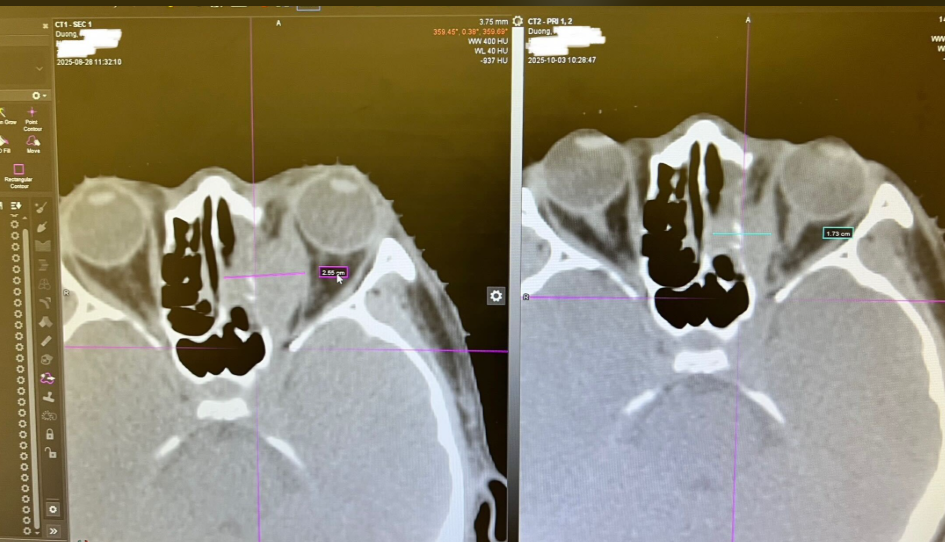

Side-by-side CT scan images of Alex Duong’s eye area, showing detailed cross-sections of the orbital region with measurement markers highlighting areas of concern. | Source: GoFundMe

Soon after, he was diagnosed with alveolar rhabdomyosarcoma, a rare and aggressive soft-tissue cancer, with a malignant mass blocking blood flow to his optic nerve.

According to a GoFundMe set up by Hilaree Steele, updates showed the road ahead was anything but straightforward. He underwent major eye surgery to remove a malignant growth, but doctors still couldn't give clear answers. There were conflicting diagnoses, uncertainty about whether he would regain his sight, and the looming possibility of another surgery.

"He recently underwent a major eye surgery to remove a malignant growth behind his eye, but instead of clear answers, he and his family have been met with uncertainty, conflicting information, and an overwhelming search for the right diagnosis and the right doctors," the GoFundMe read.